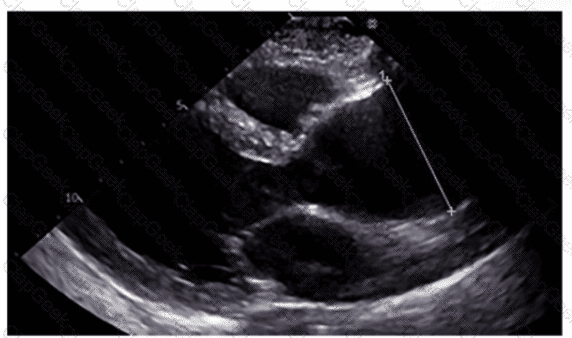

Which method of measuring left atrial size is most recommended and most accurate?

Which region of the aorta is being measured to assess the critical finding in this image?